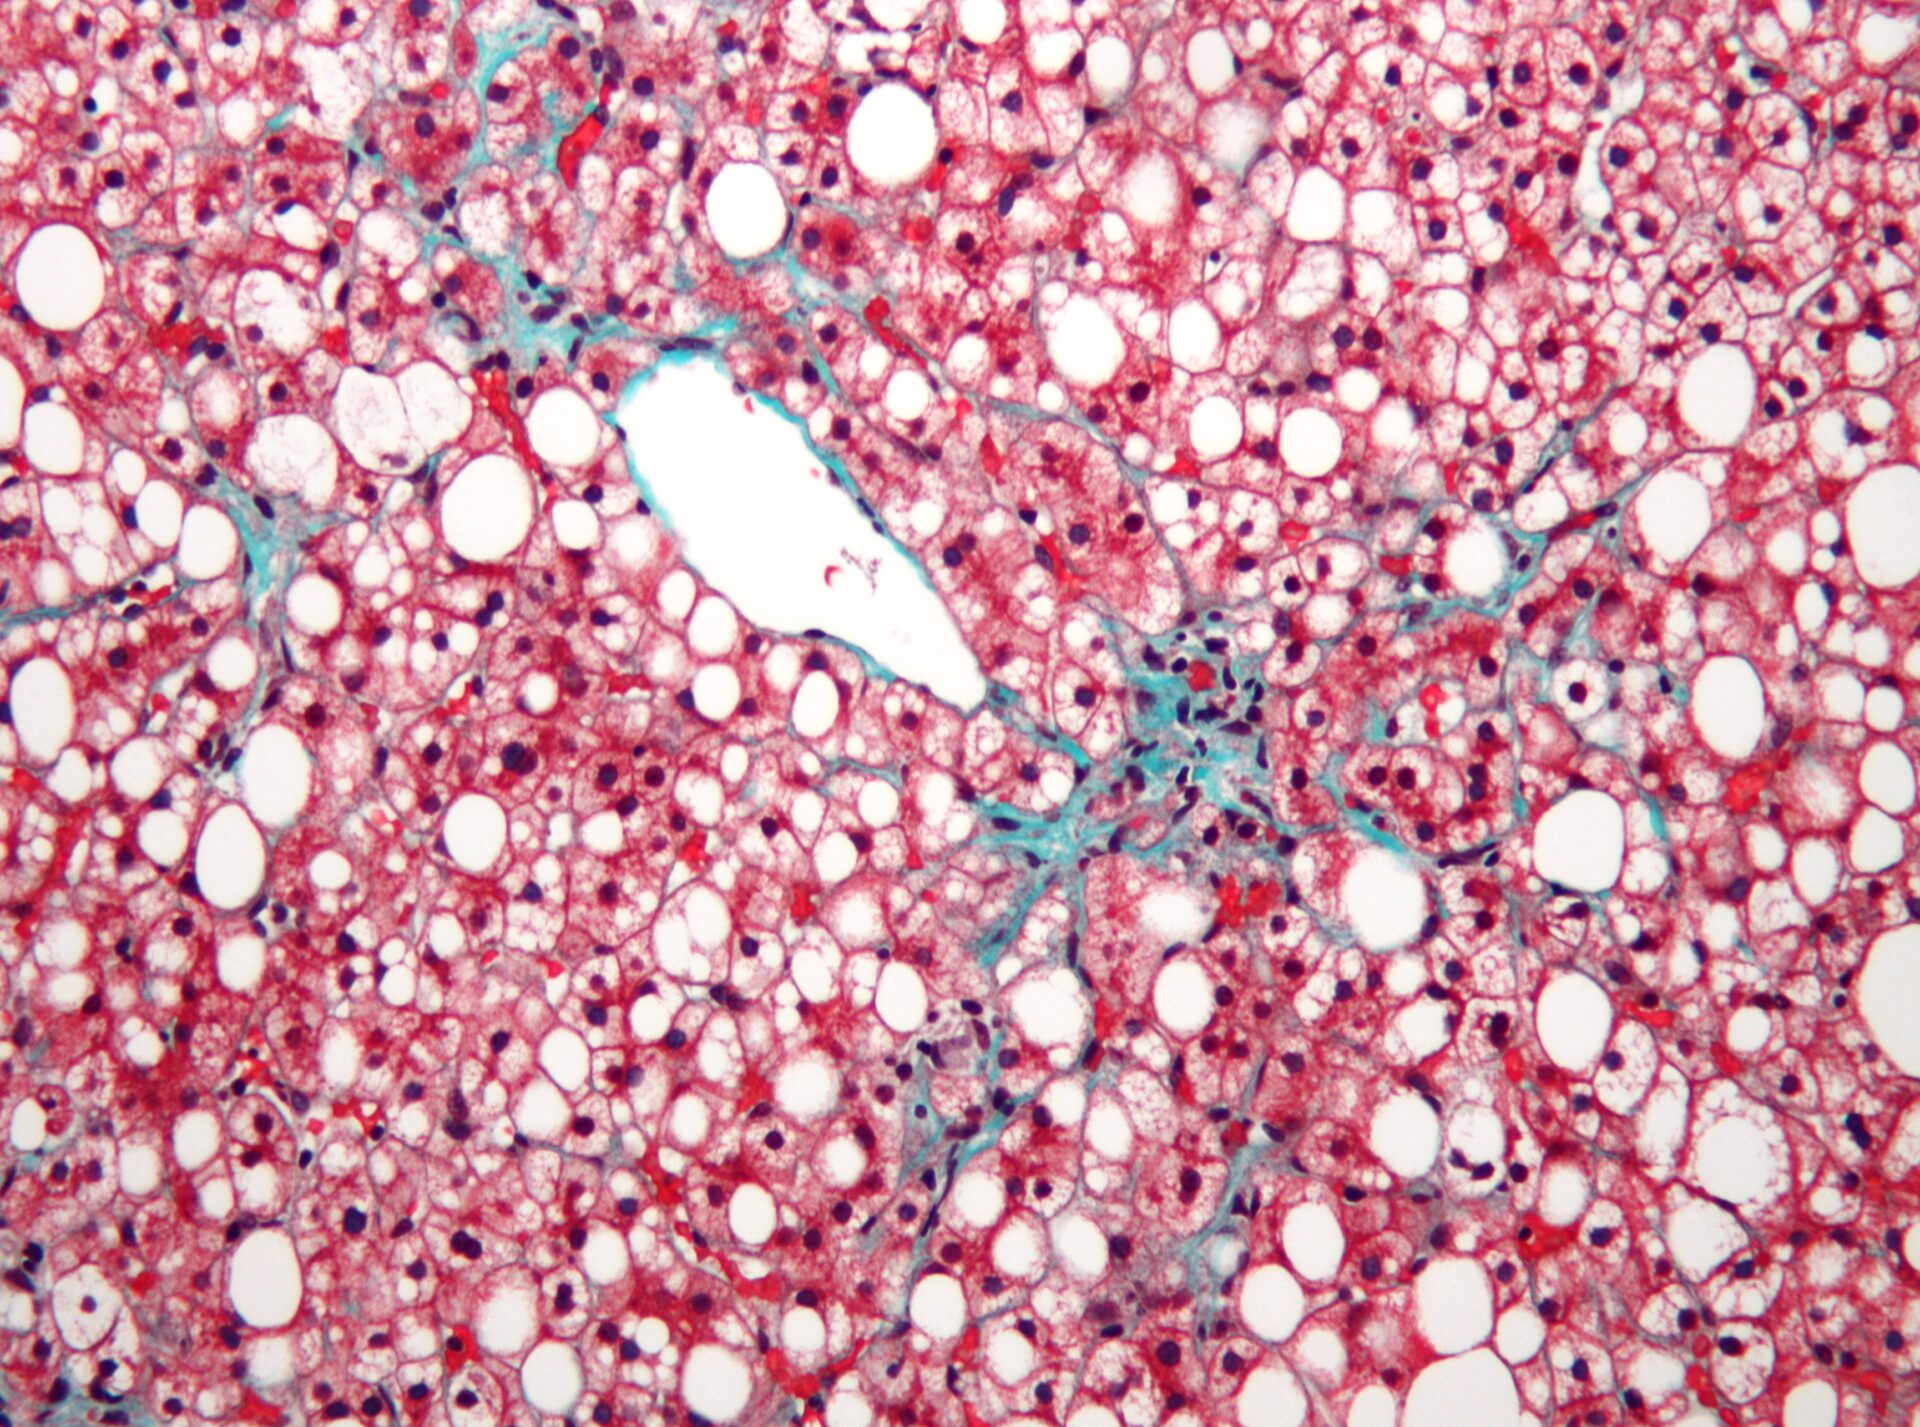

Die nicht-alkoholische Fettlebererkrankung ist weltweit die häufigste Lebererkrankung. Die 2022 aktualisierte deutsche S2k-Leitlinie empfiehlt, Risikopatienten zu screenen. Der vorgeschlagene Screening-Algorithmus sieht Fibroseabschätzung und Erfassung von Steatose als Hauptelemente vor und stimmt weitgehend überein mit den EASL-Empfehlungen. Die wichtigsten Säulen der Therapie sind Lebensstilmodifikation und Kontrolle der Komorbiditäten.